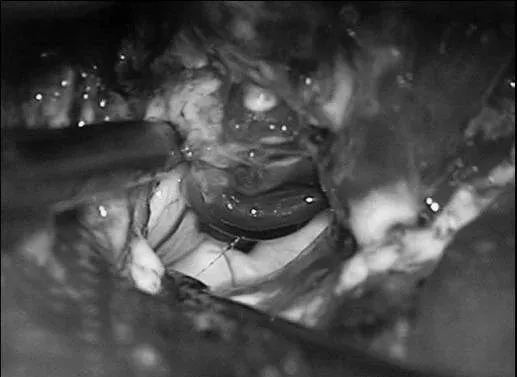

▼沿颞下回经原皮层入路达颞角

▼AChA经脉络裂进入颞角,在前方供应AVM,lPChA在后方供应AVM

▼通过ITG经皮层显露可以充分显露颞角,达到全切AVM